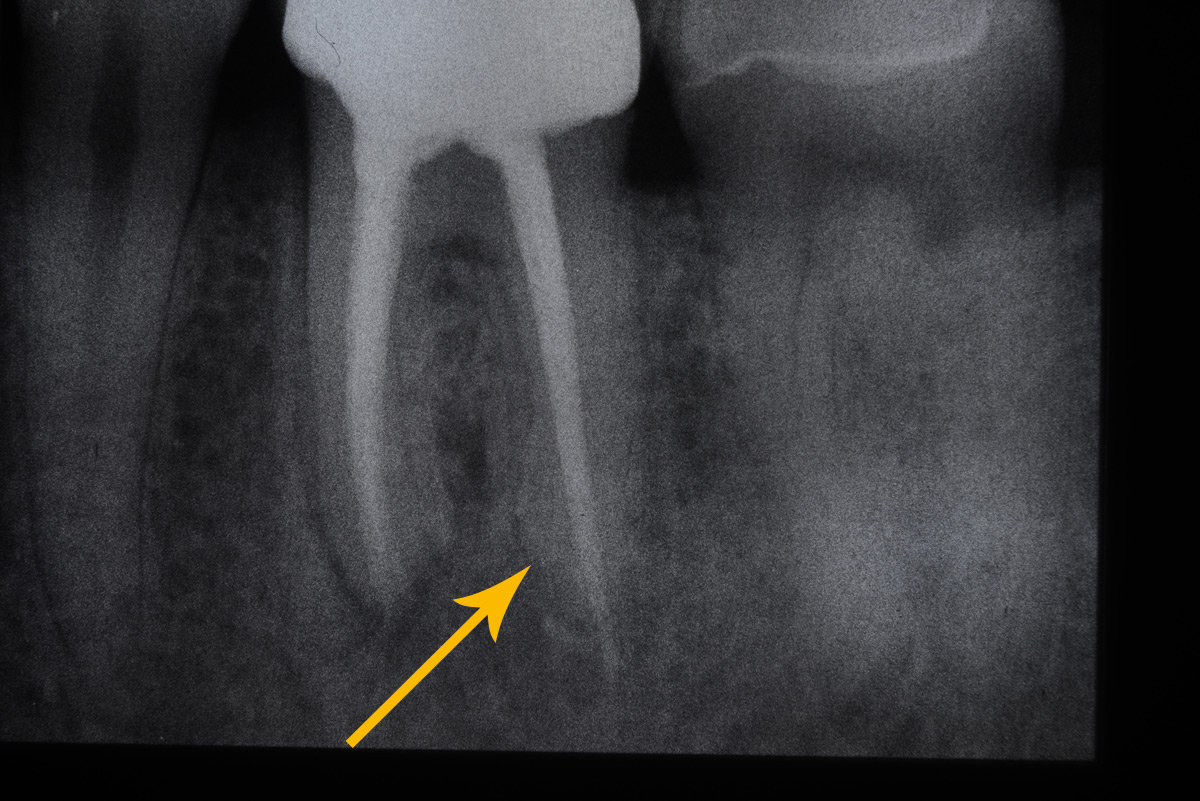

Heftige Zahnschmerzen sind die Folge, eventuell auch eine Schwellung. Der Knochen um den Zahn herum wird dadurch beschädigt, was sich im Röntgenbild als

schwarzer Schatten um die Wurzelspitze darstellt. (Bild 1)

Wenn der schwarze Schatten um den Zahn verschwunden ist (siehe Bild 4) und der Patient schmerzfrei ist, kann die Behandlung als Erfolg gewertet werden.